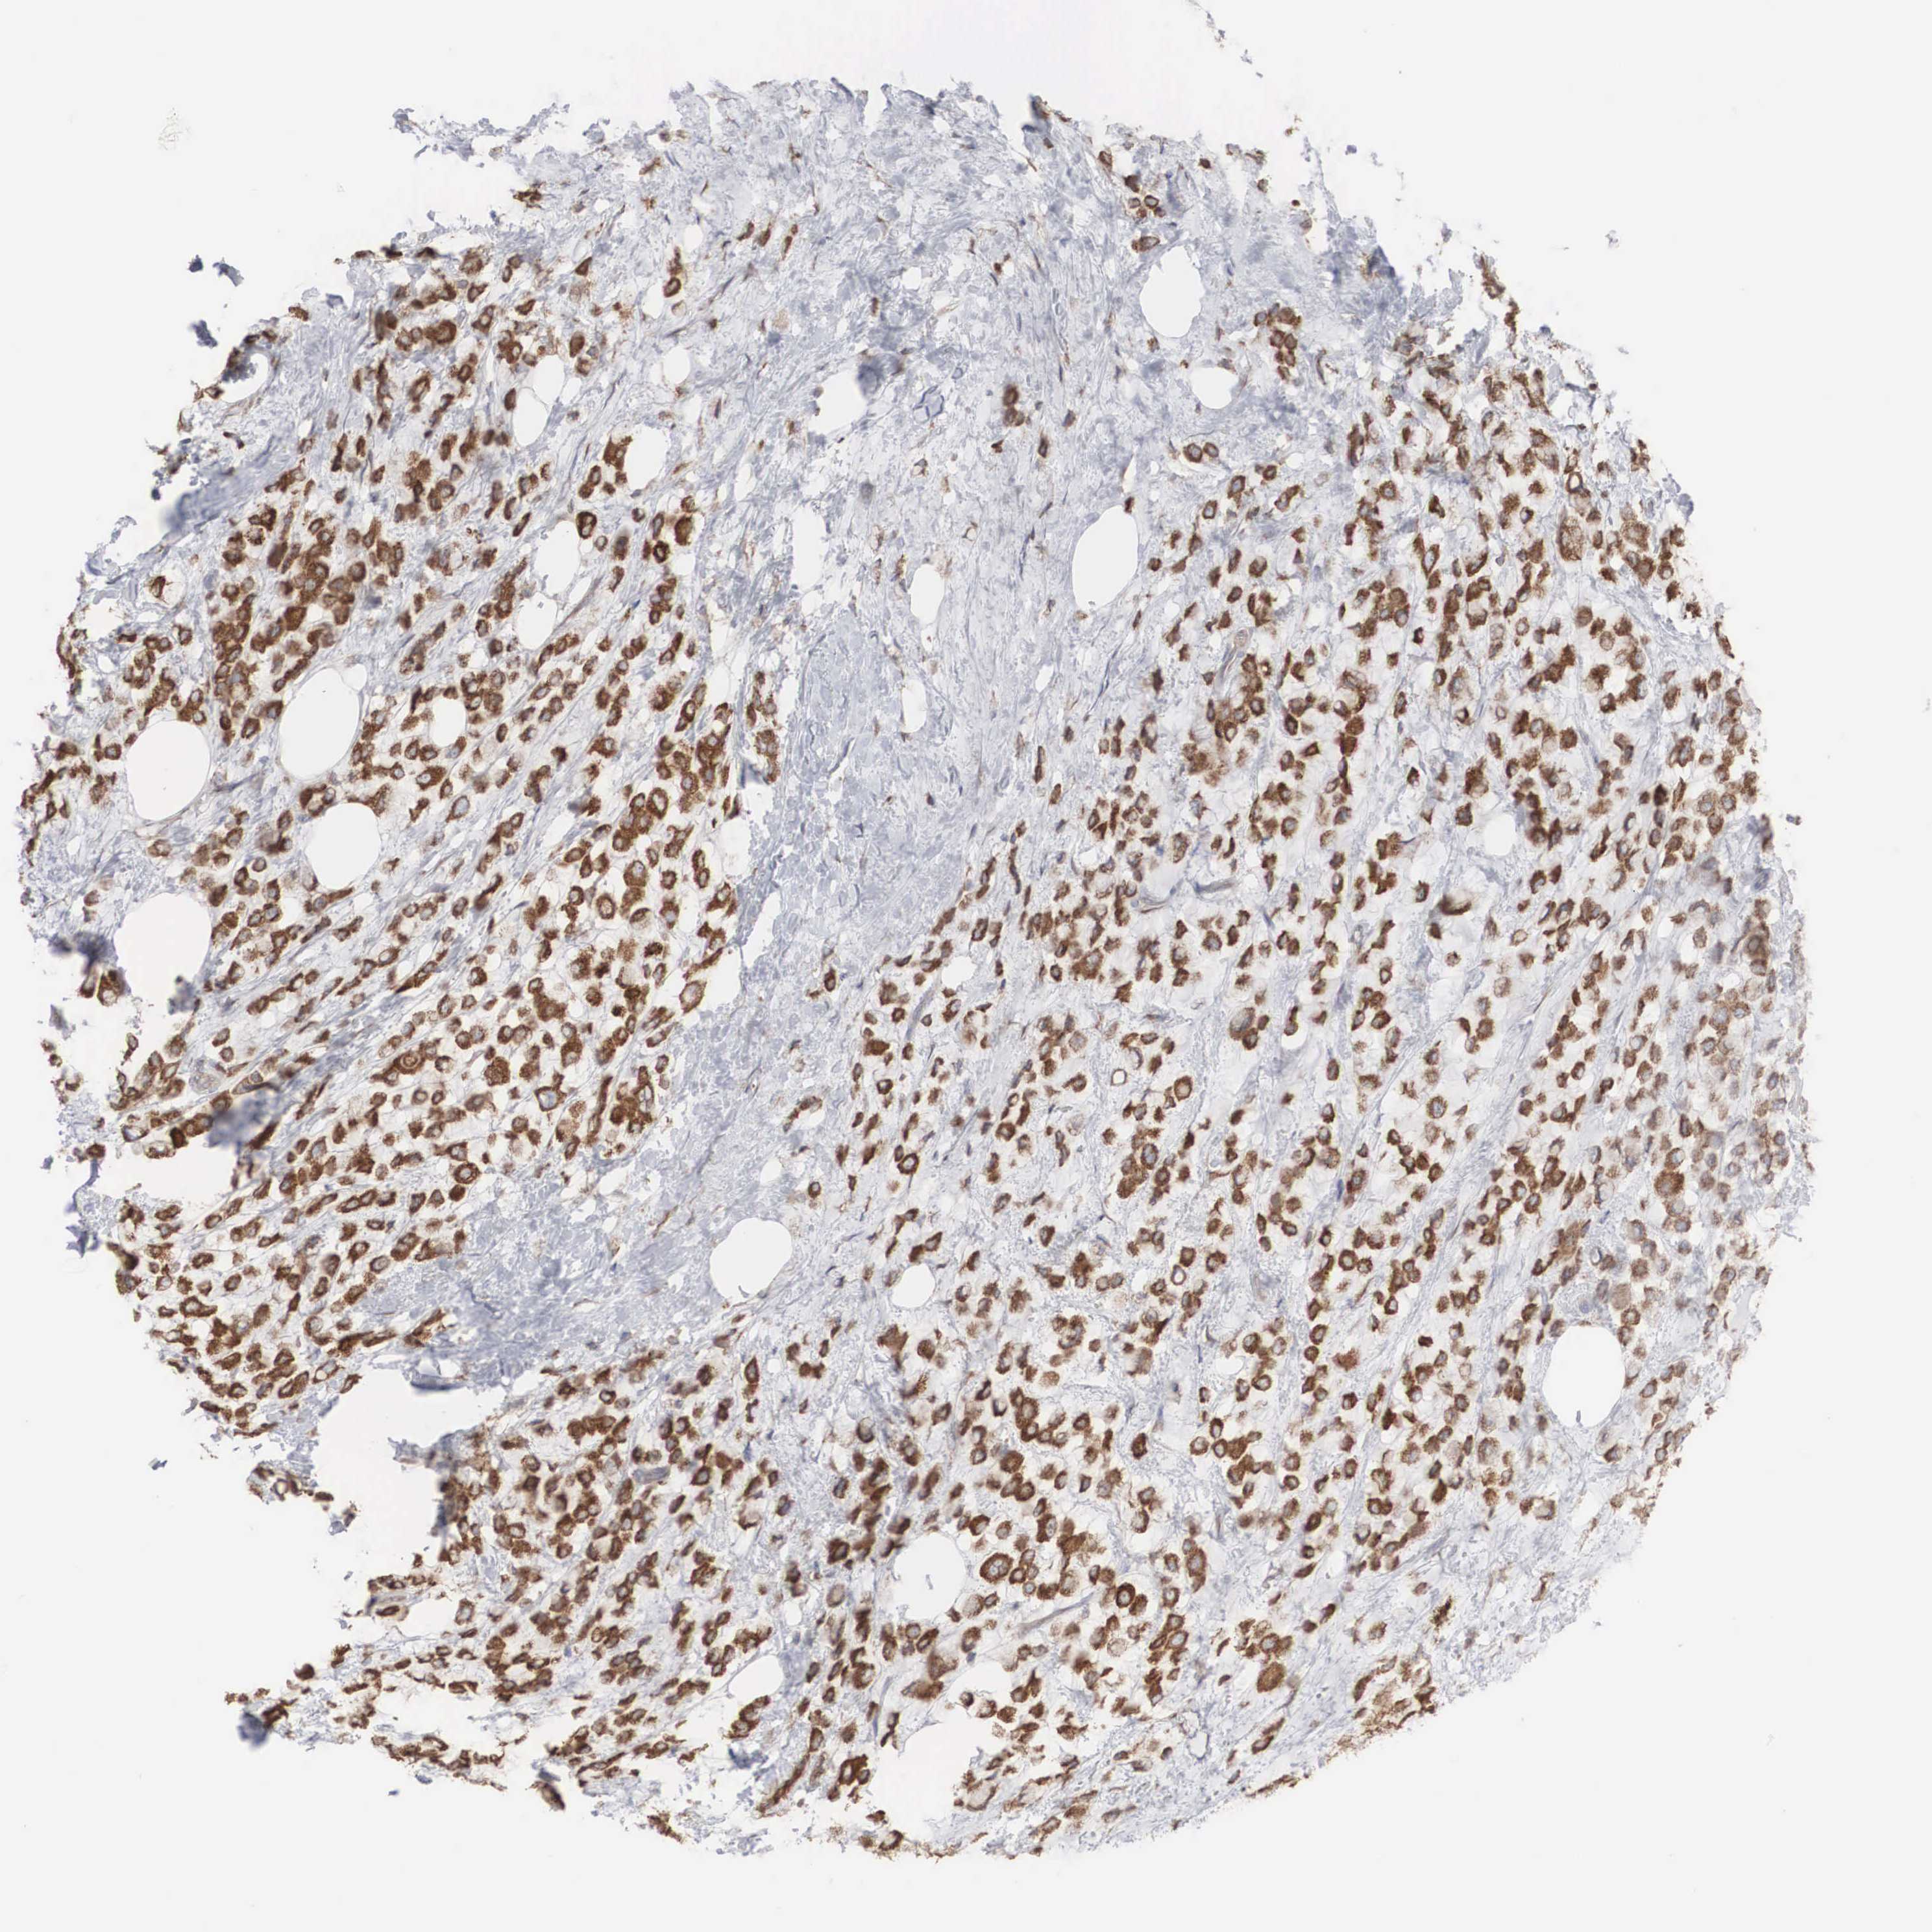

BREAST CANCER - Protein expressioni

A mouse-over function shows sample information and annotation data. Click on an image to view it in a full screen mode. Samples can be filtered based on level of antibody staining by selecting one or several of the following categories: high, medium, low and not detected. The assay and annotation is described here.

Note that samples used for immunohistochemistry by the Human Protein Atlas do not correspond to samples in the TCGA dataset.

Antibody stainingi

Antibody staining in the annotated cell types in the current human tissue is reported as not detected, low, medium, or high, based on conventional immunohistochemistry profiling in selected tissues. This score is based on the combination of the staining intensity and fraction of stained cells.

Each image is clickable and will lead to virtual microscopy that enables deeper exploration of all samples and also displays staining intensity scores, fraction scores and subcellular localization as well as patient and tissue information for each sample.

Antibody HPA000387

Antibody HPA000922

Staining

High

Medium

Low

Not detected

Intensity

Strong

Moderate

Weak

Negative

Quantity

>75%

75%-25%

<25%

None

Location

Nuclear

Cytoplasmic/membranous

Cytoplasmic/membranous,nuclear

Duct carcinoma

Lobular carcinoma

Neoplasm, malignant, NOS